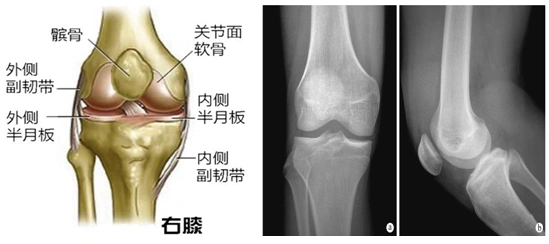

膝盖是人体最大最复杂的关节,膝关节属于铰链关节,它是我们身上少数

同时也是主要负重关节,因此它的结构失常可影响膝关节的正常力学平衡